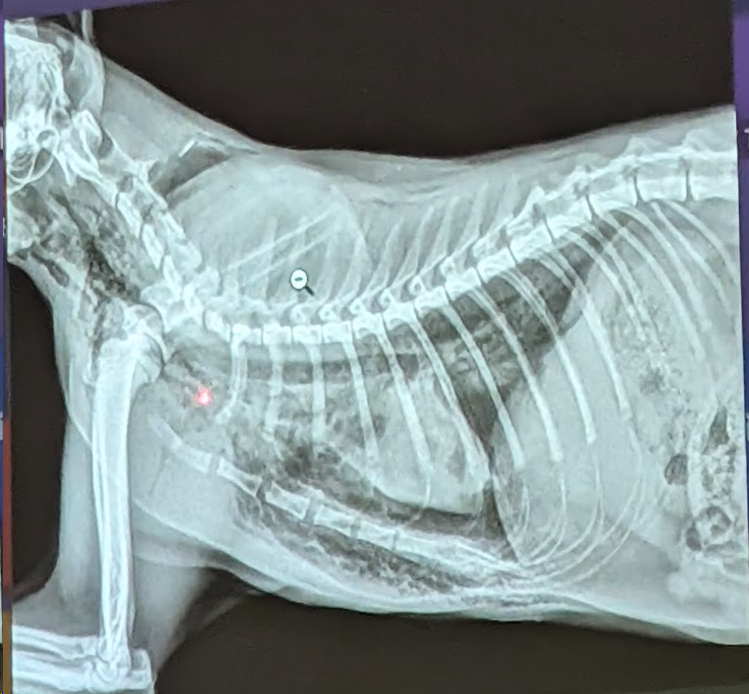

Preguna 8 - Multiple respuesta

- Enfisema subcutáneo (Aire en la piel).

- Neumomediastino (aire en la cavidad mediastinica)

- Puede haber pasado de cavidad pleural al mediastino. Puede pasar por el hiato aórtico al retroperitoneo.

NUNCA puede pasar de cavidad pleural al mediastino. Puede pasar por el hiato aórtico al retroperitoneo.